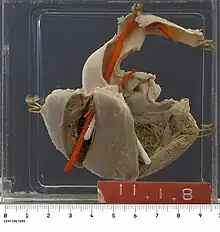

Tetralogy of Fallot with pulmonary atresia (pseudotruncus arteriosus) is a severe variant[47] in which there is complete obstruction (atresia) of the right ventricular outflow tract, causing an absence of the pulmonary trunk during embryonic development.[24]: 67–8 In these individuals, blood shunts completely from the right ventricle to the left where it is pumped only through the aorta. The lungs are perfused via extensive collaterals from the systemic arteries, and sometimes also via the ductus arteriosus.[24]: 67–8